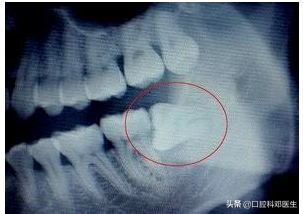

在远古时代,由于贫穷,伙食差,人类都不给他作案的机会,有足够的位置让他长出来,到了现代,随着伙食的精细,智齿常常发育不良,不是东倒就是西歪,为了报复主人,时不时发炎疼痛,让主人记住我,或者挖洞,把兄弟给祸害!

祸害兄弟

智齿行凶过程图